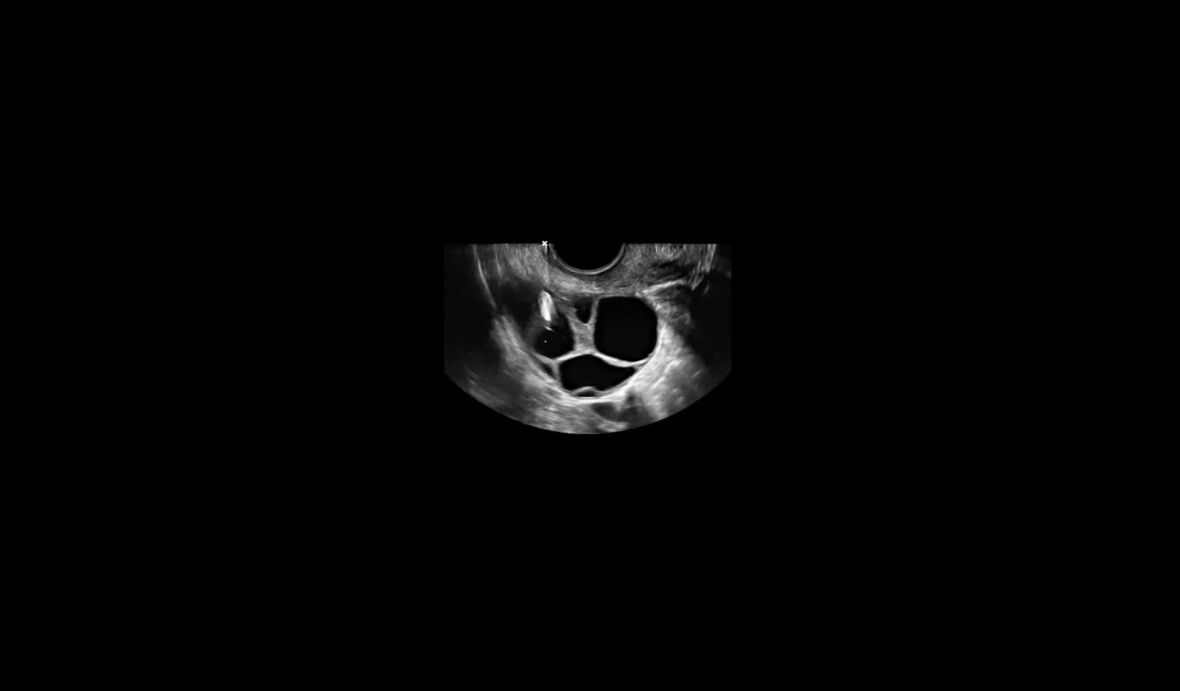

Kello tikittää ja elämä pannaan jäihin. Kuka saa saada lapsia ja millä keinoin?